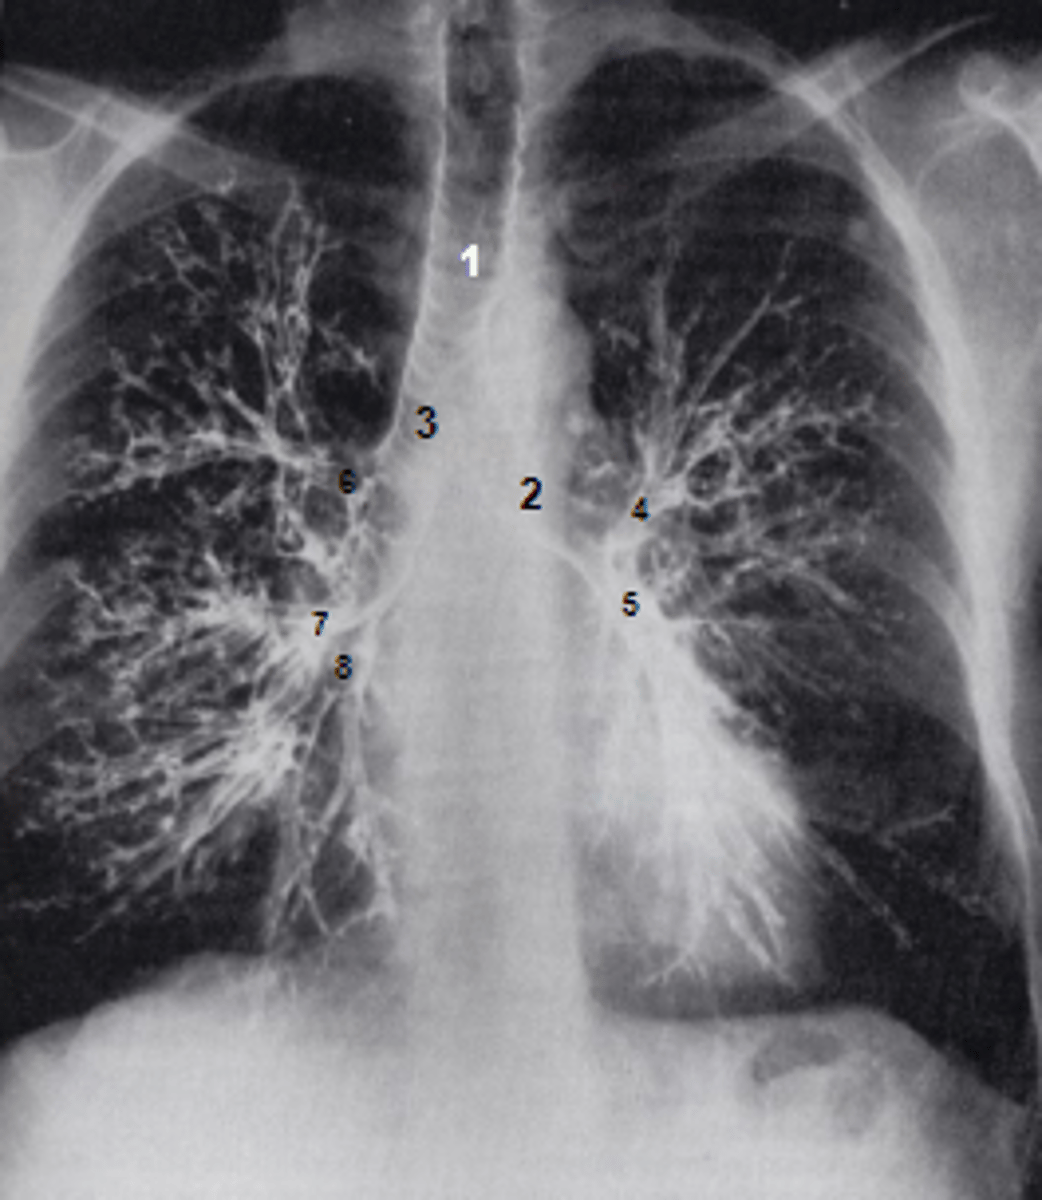

1

at what number is the trachea

2

at what number is the left main bronchus

3

at what number is the right main bronchus

4

at what number is the left superior lobar bronchus

5

at what number is the left inferior lobar bronchus

6

at what number is the right superior lobar bronchus

7

at what number is the right middle lobar bronchus

8

at what number is the right inferior lobar bronchus